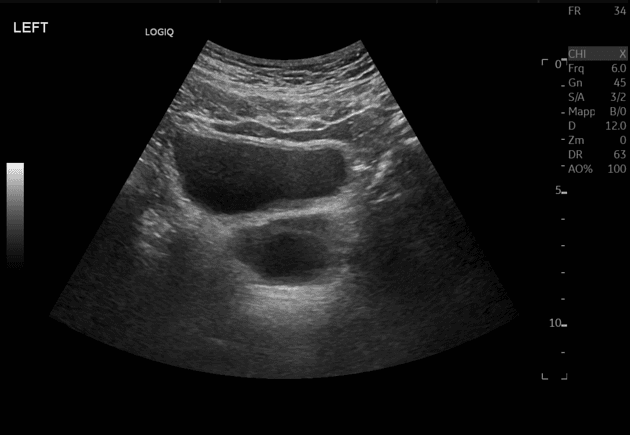

Siêu âm (Ultrasound)

- Một nang túi bầu dục tuyến tiền liệt (prostatic utricle cyst) nằm ở đường giữa (midline), giới hạn rõ (well-defined).

Nang túi bầu dục tuyến tiền liệt là sự giãn bẩm sinh của túi bầu dục, một di tích của ống cận trung thận (Müller). Đây là một nang vùng chậu nằm ở đường giữa, thông với niệu đạo sau tại vị trí gò niệu đạo. Những nang này thường được phát hiện ở trẻ em trong quá trình thăm khám các dị tật như lỗ tiểu thấp hoặc rối loạn biệt hóa giới tính. Mặc dù nhiều trường hợp không có triệu chứng, các nang lớn có thể dẫn đến nhiễm trùng đường tiết niệu tái phát, rỉ nước tiểu sau khi tiểu hoặc hình thành sỏi do ứ đọng nước tiểu. Chẩn đoán hình ảnh qua siêu âm cho thấy một cấu trúc dạng dịch ở đường giữa sau bàng quang, trong khi chụp MCUG có giá trị xác định nhờ hiển thị sự thông thương với niệu đạo.